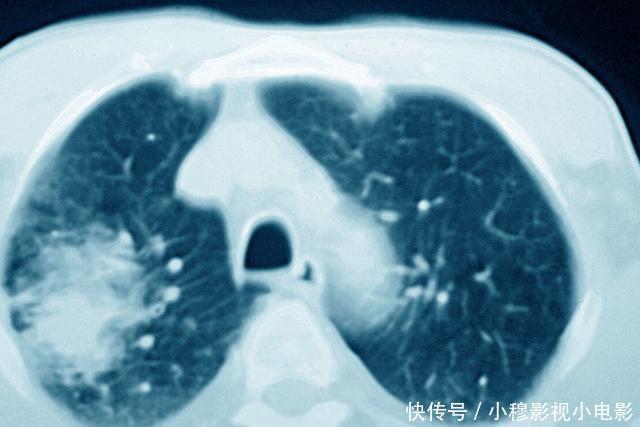

身体内长了肿瘤,那么这个肿瘤究竟有多大呢?很多时候就需要我们的CT检查来判断,CT检查通过断层成像,能够非常直观的显示肿瘤的大小,同时,CT检查还可以进行三维重建成像,这样能够非常立体的显示肿瘤的结构,还能够对肿瘤进行分期。

我们以胃癌为例,胃癌的诊断我们可以通过胃镜进行,但是为什么做了胃镜之后,医生还要给患者做CT检查呢?这主要就是因为CT检查可以显示肿瘤的大小,同时,还可以了解肿瘤的侵犯范围,比如有没有突破胃壁外缘,向腹腔内生长,周围有没有淋巴结的转移,有没有远处脏器的转移等等,这些都是胃镜检查没有办法提供的。而了解这些情况后,就可以对胃癌进行分期,因为我们一般癌症的分期是TNM分期,T代表的是肿瘤的大小,N代表的是淋巴结转移情况,M代表的是远处转移情况,而这些往往都需要通过CT进行评估。所以当发现胃癌后,医生会给患者做CT检查,评估胃癌的分期情况,从而知道下一步的治疗。如果分期比较早,没有远处转移,那么一般是可以进行手术切除的;但是如果分期比较晚,出现了比较远处转移,那么就不适合进行手术切除了,这个时候就只能采取其他的一些治疗措施,比如化疗等。所以CT检查对于临床的治疗可以说有很重要的指导意义。